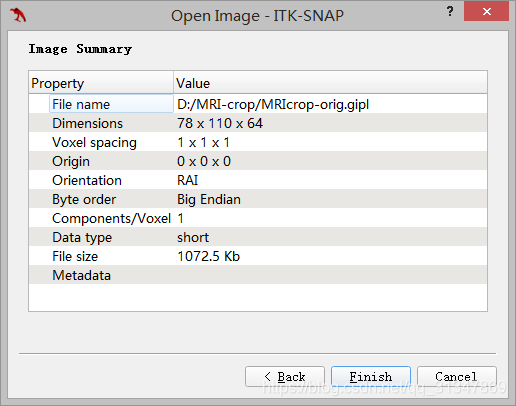

- MRIcrop-orig.gipl:大脑的原始 MRI 图像